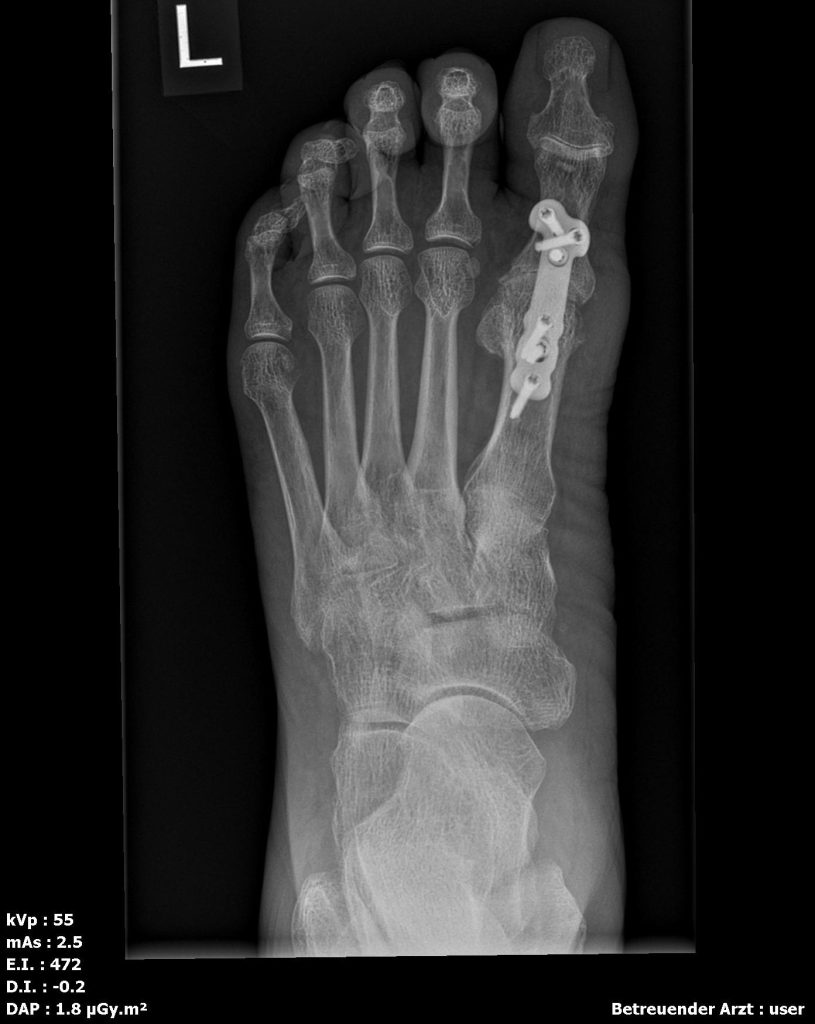

Arthrodese (Gelenkversteifung, fortgeschrittene Arthrose)

Versteifung des Großzehengrundgelenks in funktioneller Position. Sehr verlässliche Schmerzausschaltung auf Dauer, stabiles Abrollen, gute Belastbarkeit im Alltag und für viele Sportarten.

| Arthrodese | schmerzfreies, stabiles Abrollen | Beweglichkeit im MTG I: Nein | sehr verlässliche Schmerzausschaltung, hohe Belastbarkeit | fortgeschrittene Arthrose/rigidus | Entlastung einige Wochen; Entlastungsschuh 6–8 Wo.; Sport schrittweise |